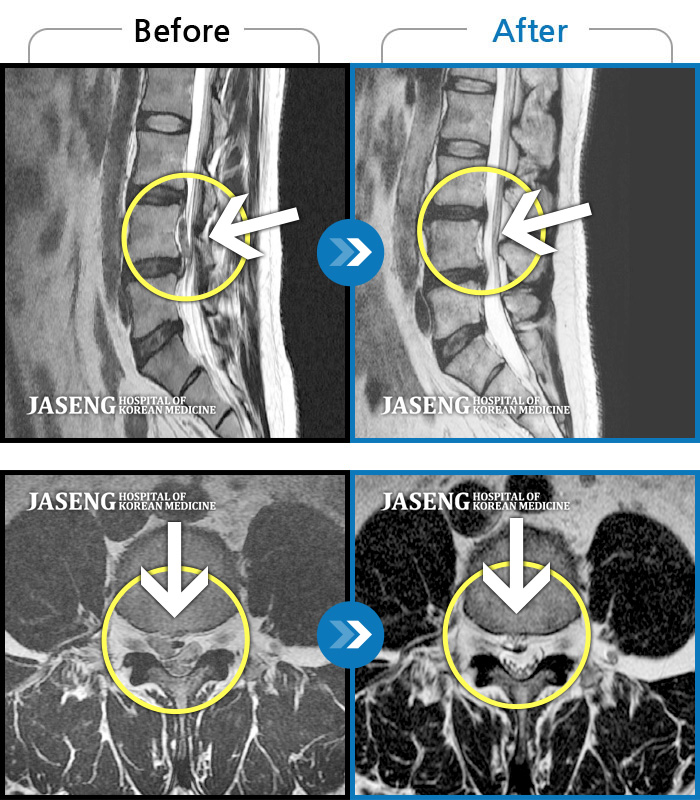

MRI 결과는 추간판협착증 2군데와 추간판탈출되어 터져서 디스크가 좌측으로 흘러내려 좌측 신경을 넓게 누르고 있는 곳이 1군데로 예상보다 심각한 상태였더군요.